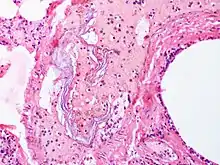

Intravascular squames are present in this example of amniotic fluid embolism.